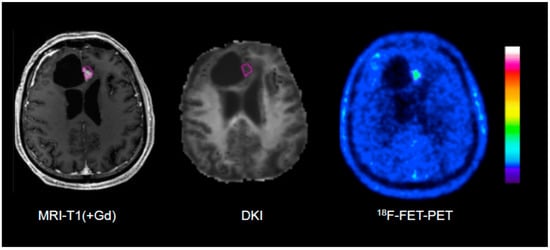

Figure 2.

Example of an 18F-FET PET-guided evaluation of diffusion kurtosis imaging (DKI) in a patient with treatment-related changes. Please note that the region of interest (pink line) generated on the PET scan (right) is larger than the area of contrast enhancement in T1-weighted MRI (left).